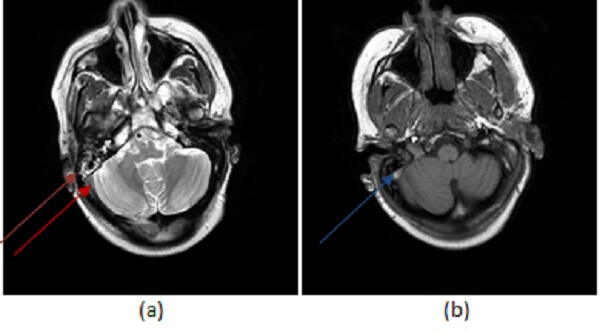

Figure 1: (a, red arrow) T2 and T1 (b,blue arrow) images demonstrate increased signal in the right sigmoid sinus. This finding could be due to either thrombosis or slow venous flow. There is also fluid in the mastoid air cells (purple arrow)- while fluid in the mastoid air cells is typically sterile, fluid can reflect infection in the case of mastoiditis, and mastoiditis predisposes to venous thrombosis.(c,green arrow) 3-D reconstructions from an MR venogram demonstrate abrupt cut off of contrast in the right transverse sinus with the suggestion of collateral flow (brown arrow) more consistent with thrombosis.

Diagnosis is typically made on imaging. It can be suggested on conventional MRI with abnormal signal in the venous sinuses. Typically, the sinuses should demonstrate dark flow voids on T1 and T2 imaging. On a given T1 or T2 sequence, the sinus may not be completely dark due to inflow effects, motion and other artifacts. However, persistent increased signal in the venous sinus on T1 and T2 imaging raises the question of an abnormality – either slow flow in the sinus or thrombosis.

If there is clinical or imaging suspicion for venous sinus thrombosis, a CT venogram or MR venogram should be performed. These studies provide better delineation of the sinuses and are typically performed with contrast. A common pitfall in the diagnosis is dural sinus thrombosis is the hypoplastic transverse sinus which can mimic occlusion. Thrombosis typically causes a frayed appearance to the venous sinus that may be associated with collaterals.